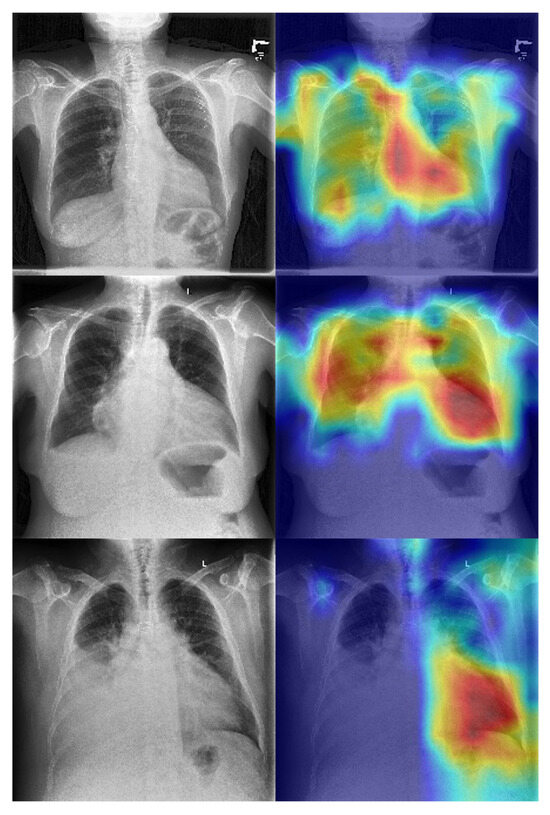

The superior performance of the ViT model is likely driven by its global self-attention mechanism, which enables modeling of long-range anatomical dependencies across the thoracic cavity, a capability that convolutional architectures lack due to their reliance on localized receptive fields. These findings establish that SLVH-relevant cues are sufficiently encoded in chest radiographs to support high-accuracy direct classification when leveraging appropriate architectural priors and pretraining strategies. We show some exemplar GRADCAMs here to further strengthen the interpretability of model decisions in Figure 5. Across multiple examples, we observe that the model consistently attends to central cardiac regions, particularly the mediastinum and left ventricular silhouette, with high-intensity activations (red regions). This localization aligns with the expected anatomical correlate of severe left ventricular hypertrophy, where cardiac enlargement and changes in ventricular wall thickness manifest most prominently in these areas. Importantly, the activations are concentrated around the cardiac contour rather than diffuse pulmonary fields or image borders, suggesting that the network is not relying on spurious features such as rib patterns, background artifacts, or acquisition markers. These interpretability results reinforce the clinical plausibility of the learned features and provide additional transparency. They suggest that the model’s predictions are informed by relevant cardiothoracic structures, in agreement with radiological and cardiological understanding of hypertrophy, thereby increasing confidence in its potential utility.

Figure 5.

Grad- CAM activation maps for enhanced interpretability on our ViT backbone.